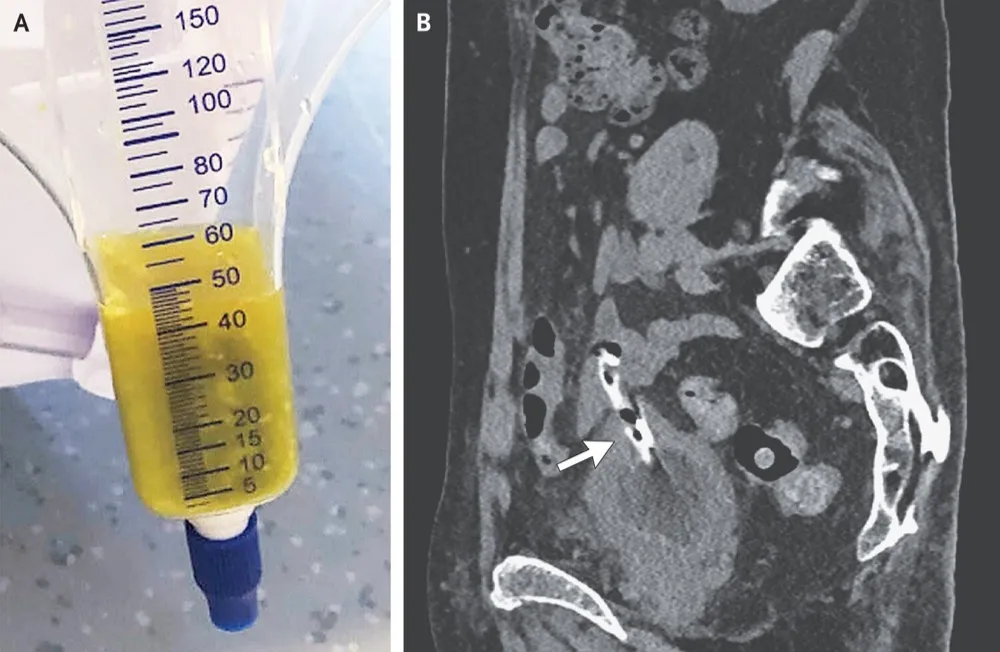

IRA com ascite: Deve ser uma síndrome hepatorrenal, certo? Descubra como uma perfuração vesical após radioterapia pode simular lesão renal aguda e aprenda a identificar esse raro diagnóstico diferencial em nefrologia

Valkercyo Feitosa

2 anos atrás

Fístula urinária como complicação de um cateter uretral, vale a pena a leitura dessa caso clínico publicado no NEJM

Valkercyo Feitosa

2 anos atrás